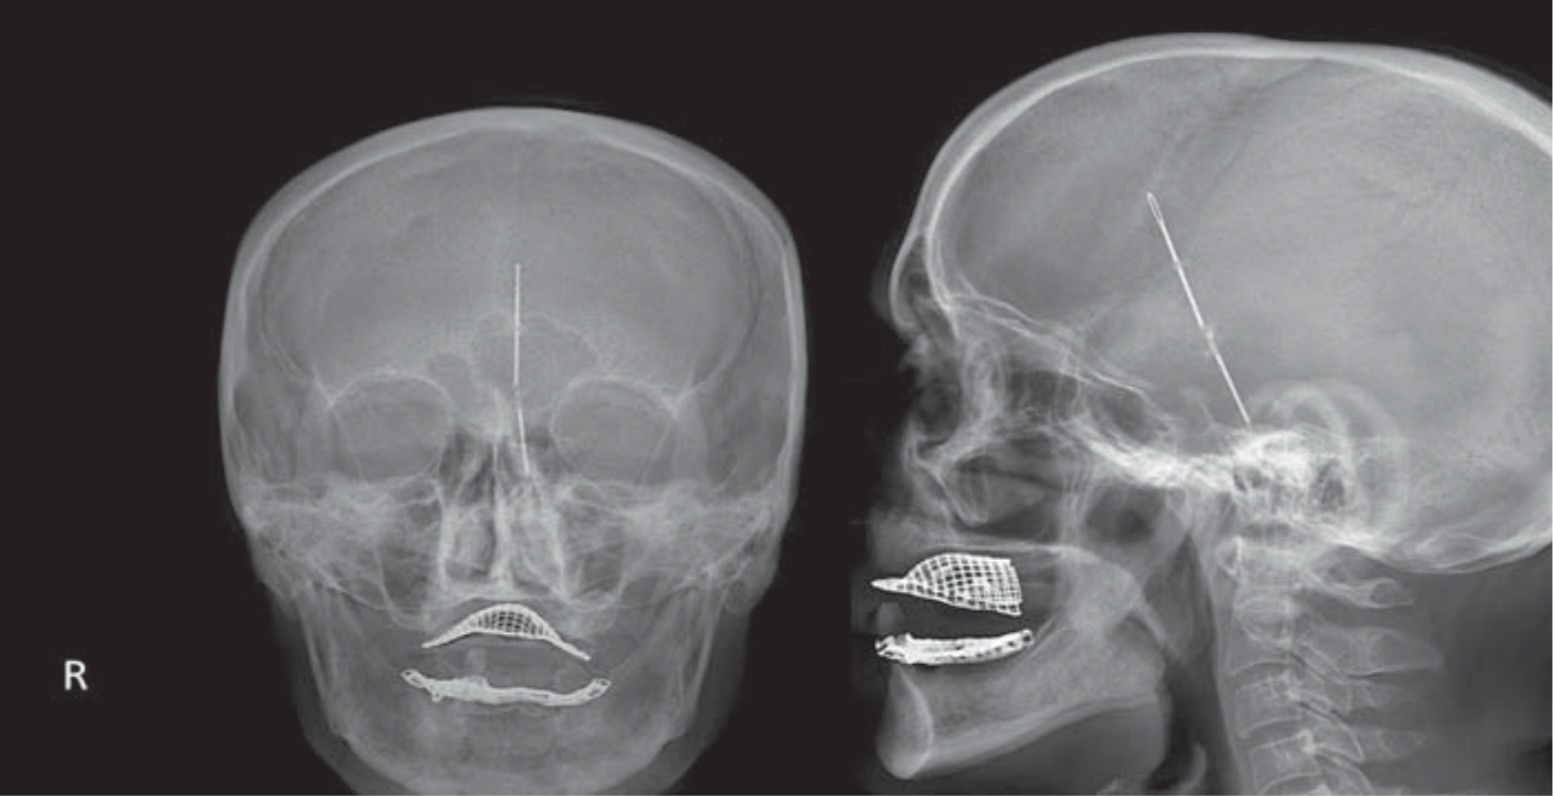

Figure 1. Рентген снимок, демонстрирующий швейную иглу.